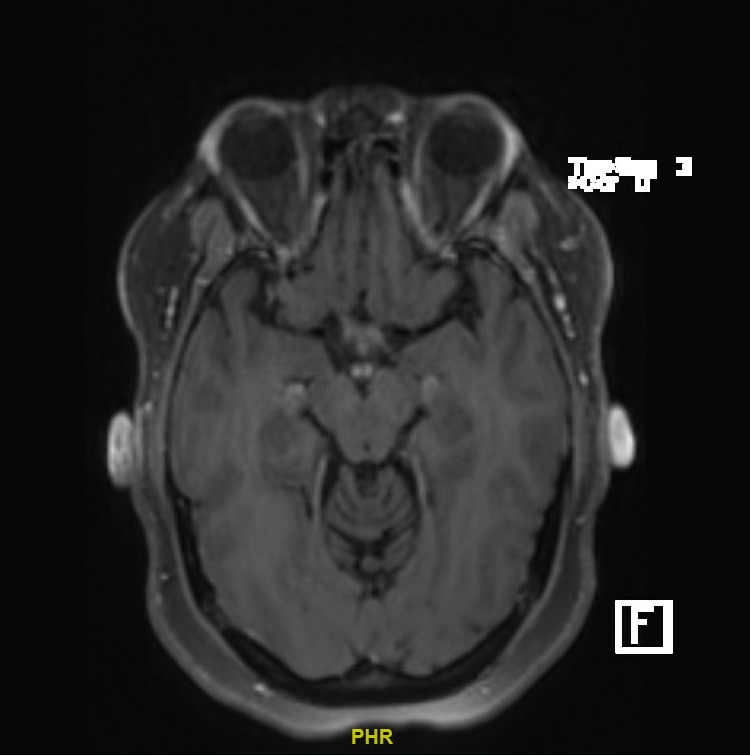

This patient’s findings are most consistent with a diagnosis of thiamine deficiency secondary to celiac disease. The mammillary body enhancement seen on magnetic resonance imaging (MRI) is a key diagnostic finding of thiamine deficiency. Additionally, this patient’s nausea and vomiting, distal paresthesias, ascending muscle weakness, and gait ataxia are common sequelae of thiamine deficiency. Although manifestations of thiamine deficiency vary, the absence of oculomotor dysfunction, nystagmus, and encephalopathy are more consistent with dry beriberi than Wernicke’s encephalopathy. The constellation of lab derangements indicates this patient has additional protein and vitamin deficiencies, leading me to believe this patient has an underlying malabsorptive disorder, likely celiac disease. This is also consistent with her gastrointestinal symptoms and weight loss. My workup would include serum and urine thiamine levels, as well as serum B6, B12, folate, zinc, vitamin D, and iron levels. I would also initiate a workup for celiac including a serum tissue transglutaminase IgA level and total IgA level. If the serology is positive, I would confirm the diagnosis via duodenal biopsy.

Dr. Daniel Mandel – Radiology Review

Post contrast MRI brain sequence revealed bilateral mamillary body gadolinium enhancement. Gadolinium enhancement reflects disruption of the blood-brain barrier. There is no evidence of involvement of other brain structures. This finding is classically associated with Wernicke’s encephalopathy, a condition arising from thiamine deficiency and is detected in 40-50% of cases. It may be accompanied by changes on MRI in the periaqueductal gray matter and thalamic nuclei which are not seen here. Isolated changes to the mammillary bodies are unusual.

Thiamine deficiency is a laboratory diagnosis based on thiamine blood levels or erythrocyte thiamine transketolase activity (ETKA). MRI imaging shows bilateral enhancement of the mamillary bodies in 58% of patients.4 Treatment of thiamine deficiency with IV thiamine repletion should be initiated as soon as clinical suspicion arises, followed by oral supplementation.5 Wet/dry beriberi and WE improve with timely thiamine repletion, whereas KS is irreversible.